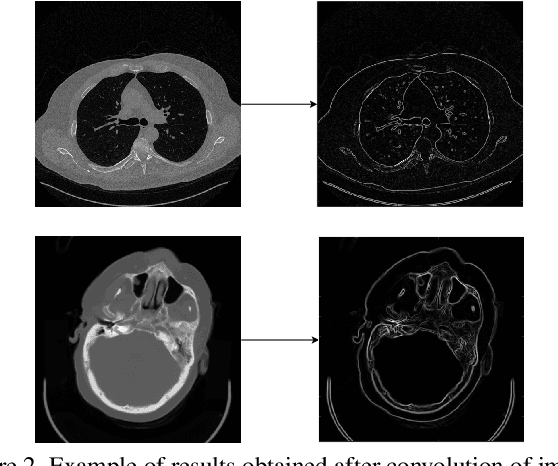

Abstract:In this work, we present Eformer - Edge enhancement based transformer, a novel architecture that builds an encoder-decoder network using transformer blocks for medical image denoising. Non-overlapping window-based self-attention is used in the transformer block that reduces computational requirements. This work further incorporates learnable Sobel-Feldman operators to enhance edges in the image and propose an effective way to concatenate them in the intermediate layers of our architecture. The experimental analysis is conducted by comparing deterministic learning and residual learning for the task of medical image denoising. To defend the effectiveness of our approach, our model is evaluated on the AAPM-Mayo Clinic Low-Dose CT Grand Challenge Dataset and achieves state-of-the-art performance, $i.e.$, 43.487 PSNR, 0.0067 RMSE, and 0.9861 SSIM. We believe that our work will encourage more research in transformer-based architectures for medical image denoising using residual learning.